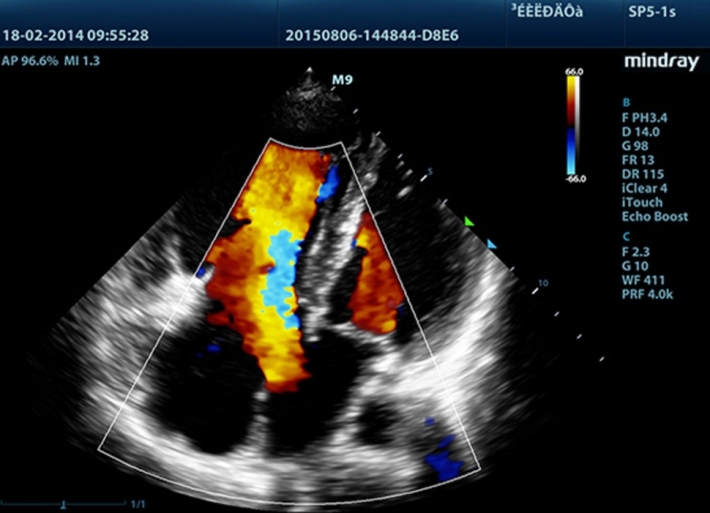

Медицинское оборудование и сервисное обслуживание